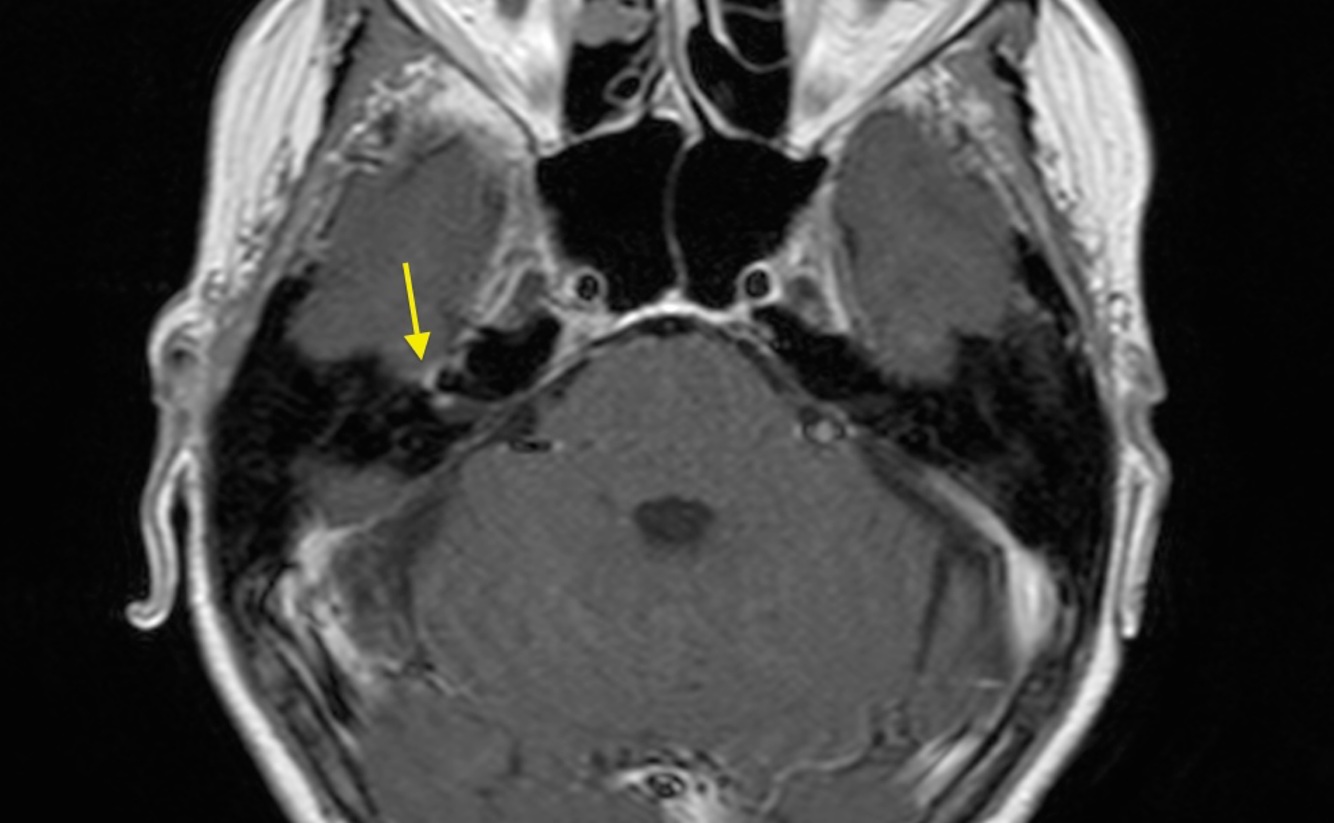

An MRI of Bell’s palsy, may reveal ___.

An MRI of Bell’s palsy, may reveal contrast enhancement of the facial nerve.